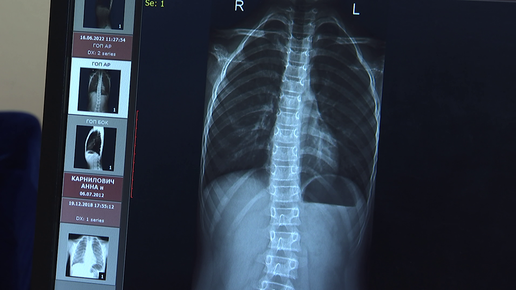

Синдром гипермобильности суставов: диагностика и современные методы лечения

Что такое гипермобильность суставов и когда это небезопасно? Поговорили с детским ортопедом